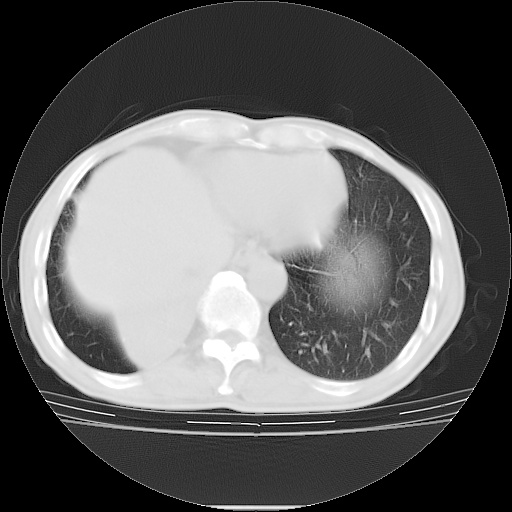

男性患者,63岁。右侧胸背部疼痛2月,加重一周。

还有----下叶不张   挺典型

右下肺中心型肺癌并肺不张

考虑右中心型肺癌并右下肺不张,肺及纵隔,左肋骨转移。

右肺下叶支气管狭窄闭塞,右下肺不张,气管前间隙淋巴结肿大,两上肺散在分部粟粒灶,沿肺血管支气管束分部,血管支气管束走形较为光滑。考虑右肺中心型肺癌合并肺不张,纵隔淋巴结转移,两上肺癌性淋巴管炎

右肺下叶中心性肺癌并纵隔淋巴结转移,左侧肋骨转移。双肺上叶继发性结核表现。

1)右肺下叶中心性肺癌并纵隔淋巴结转移,两肺转移,左侧肋骨转移。2)双肺上叶继发性结核。